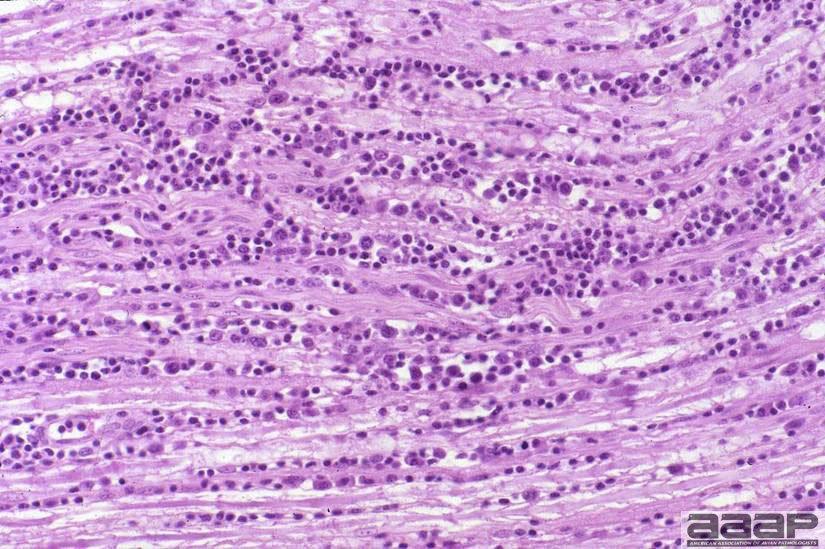

[FONT=Arial,Bold][FONT=Arial,Bold][FONT=Arial,Bold]Fig. 12; Marek's Disease; UC Davis [/FONT]Nerve infiltration (HP) HL Shivaprasad; CAHFS, UC Davis[/FONT][/FONT]​